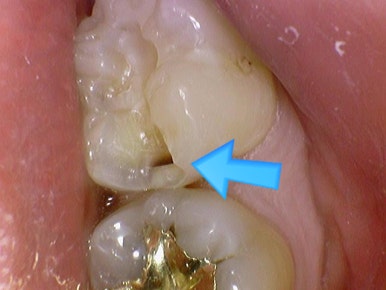

[아래 사진은 환자분이 공개에 동의한 사진입니다]

왼쪽처럼 겉에서는 멀쩡해보이는 치아도 파보면 충치가 있는 것을 확인할 수 있습니다.

위 사진에서 보듯이 왼쪽처럼 겉에서는 멀쩡해보이는 치아도 파보면 충치가 있는 것을 확인할 수 있습니다.

보여주는 치료.

이렇게 깊은 충치들을 사진을 찍어서 보여드리기 때문에 환자분들이 충치치료를 하고도

왜 충치가 안보이는데 치료를 했지? 라는 찝찝함을 없애드립니다.